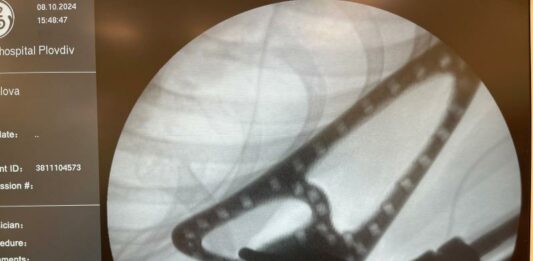

За първи път в България, 11-годишно момиче ще има възможност да движи отново рамото и ръката си благодарение на уникална операция, извършена в УМБАЛ „Еврохоспитал“-Пловдив. Екип от водещи ортопеди-хирурзи успешно премахна злокачествен тумор на дясната лопатка и раменна кост на пациентката и замести отстранените части с индивидуално създадена 3D принтирана ендопротеза. Иновативно решение за сложен … Продължете с четенето на За първи път в България: 11-годишно момиче ще движи рамото си благодарение на 3D принтирана ендопротеза